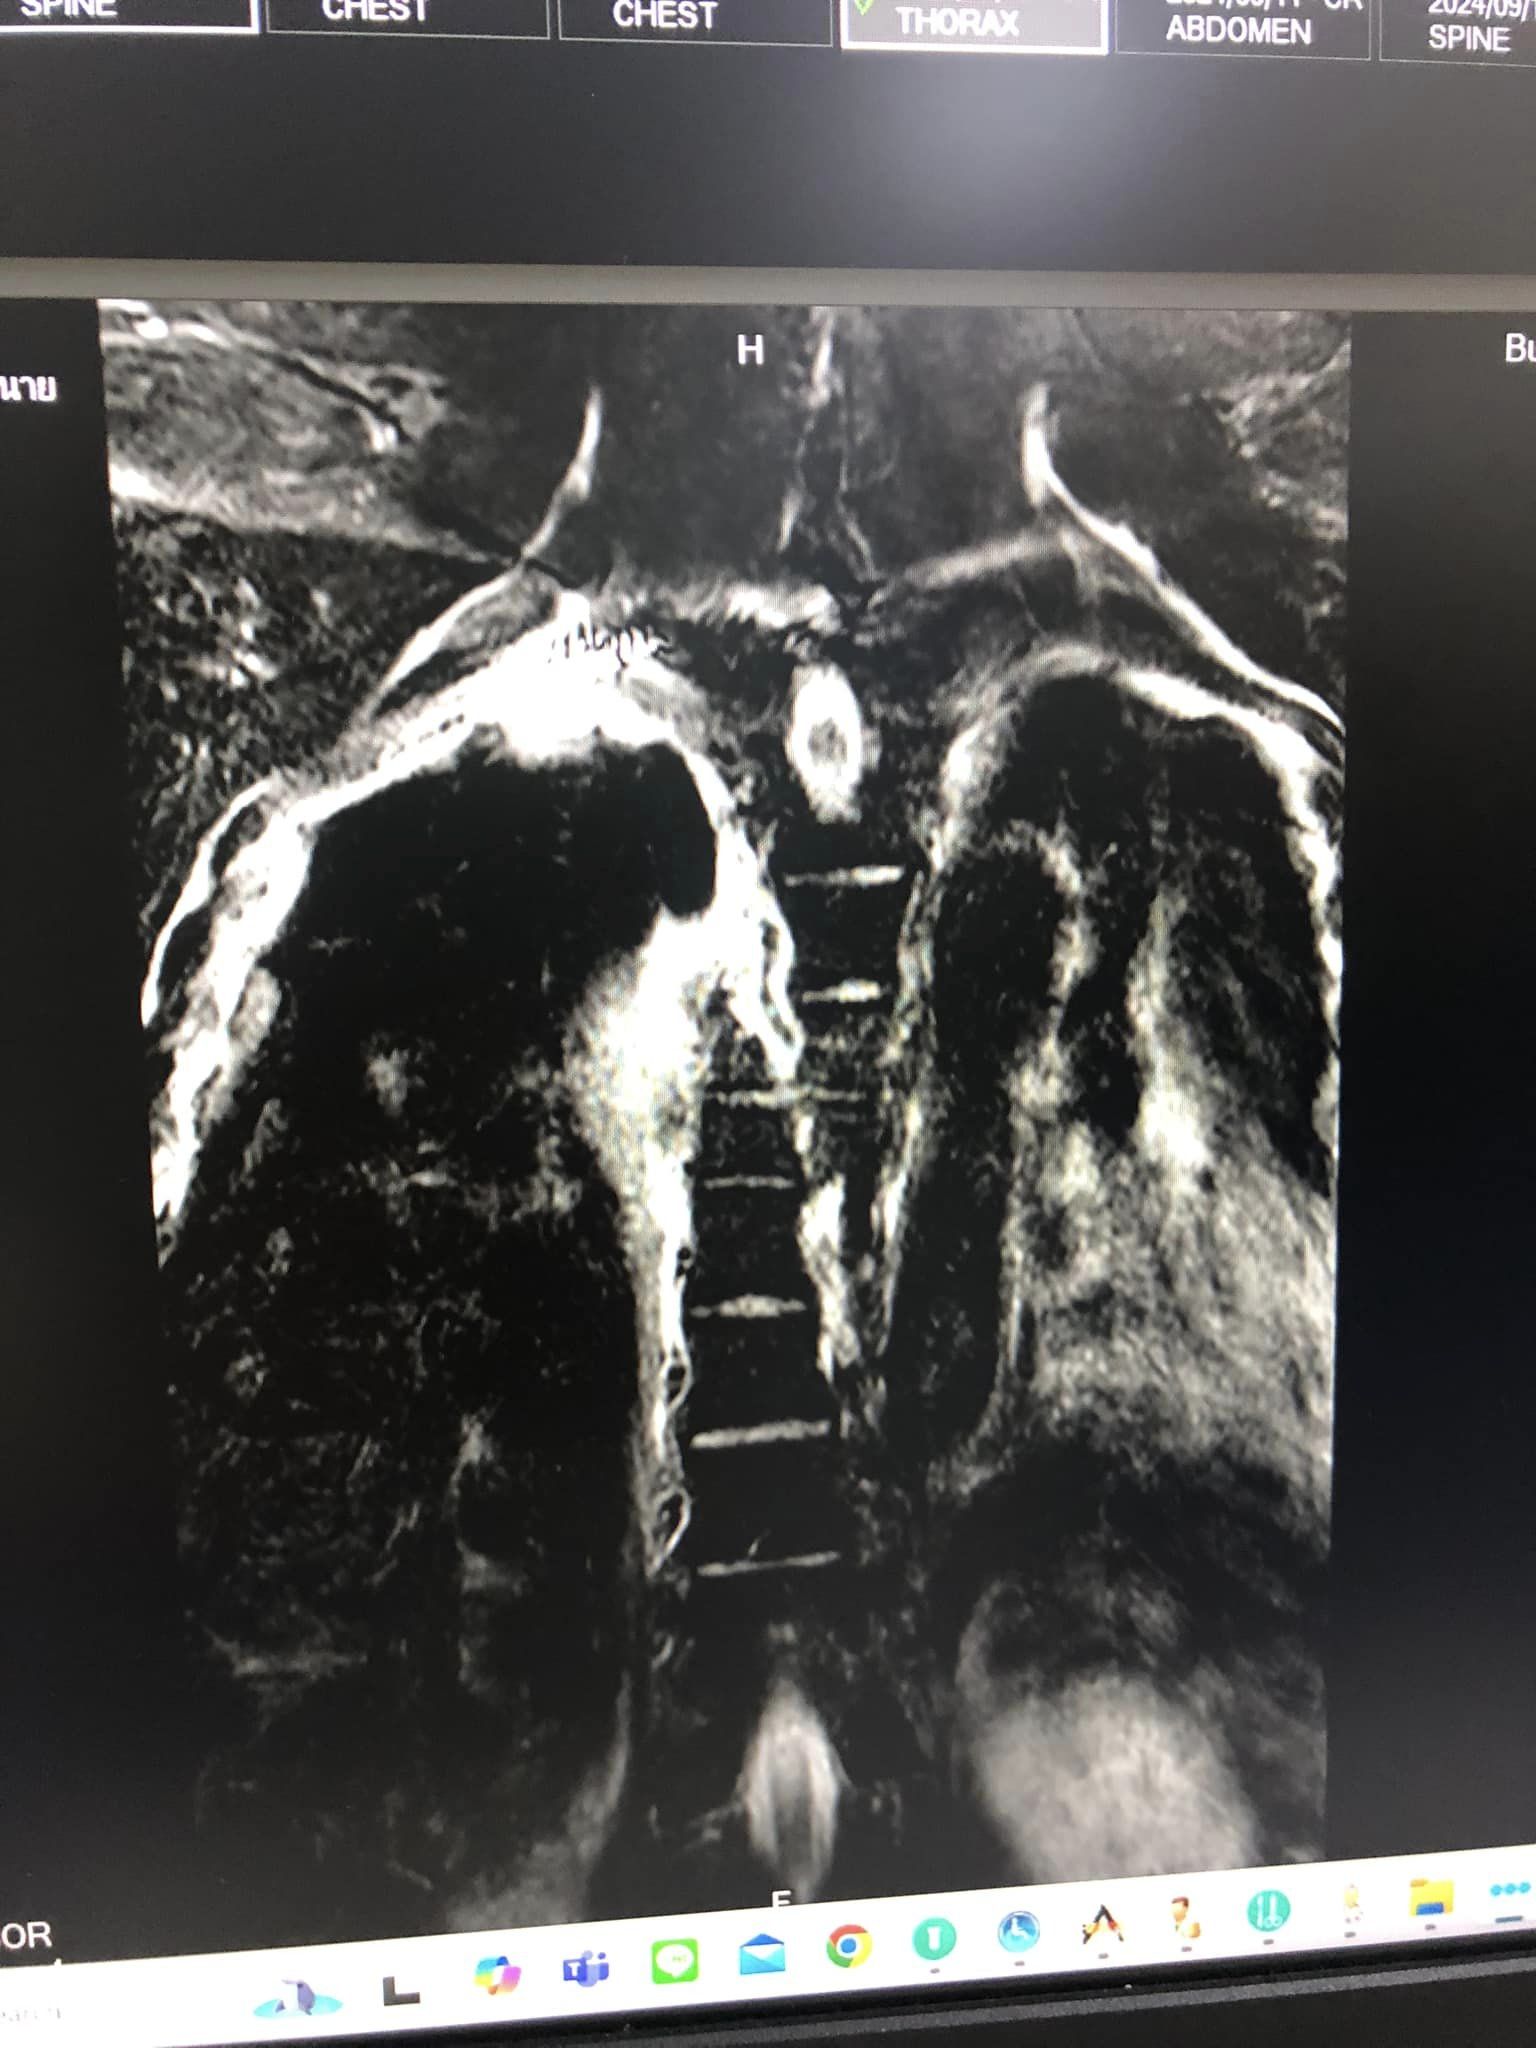

ต่อมา หญิงลี ก็ได้โพสต์เฟซบุ๊ก เป็นภาพเอกซเรย์ของแฟนหนุ่ม ภาพแฟนหนุ่มที่โรงพยาบาล และภาพของตนเองที่ไปดูรถที่เกิดเหตุ พร้อมข้อความว่า "สู้และอดทนมาก ๆ นะ กระดูกสันหลังหัก ส่วนล่างขาไม่รู้สึก พรุ่งนี้ผ่าตัด กลับมาเดิน และทำงานกันนะไม้ อุบัติเหตุ หลับใน โชคร้ายมาให้สุดไปเลยปีนี้ #หญิงลี มีอีกไหม ปัญหา มาคัก ๆ ซะ"

จากนั้นแฟนหนุ่มถูกส่งมายังโรงพยาบาลบุรีรัมย์ ตนก็นั่งรถจากกรุงเทพฯ มาถึงโรงพยาบาล แฟนเข้ารับการรักษาในโซนไอซียูแผนกทรวงอก เพราะเกิดการเลือดออกจากทางทรวงอก ระบบหัวใจ คุณหมอให้ข้อมูลเบื้องต้นว่าภาวะเกร็ดเลือดต่ำ ความดันต่ำ มีภาวะจะช็อกตลอดเวลา อยู่ในอาการโคม่าของเมื่อวานนี้สามารถจะช็อกเสี่ยงเสียชีวิตได้ตลอดเวลา ปอดฉีก ที่สำคัญคือกระดูกสันหลังหักประมาณ 4 ท่อน